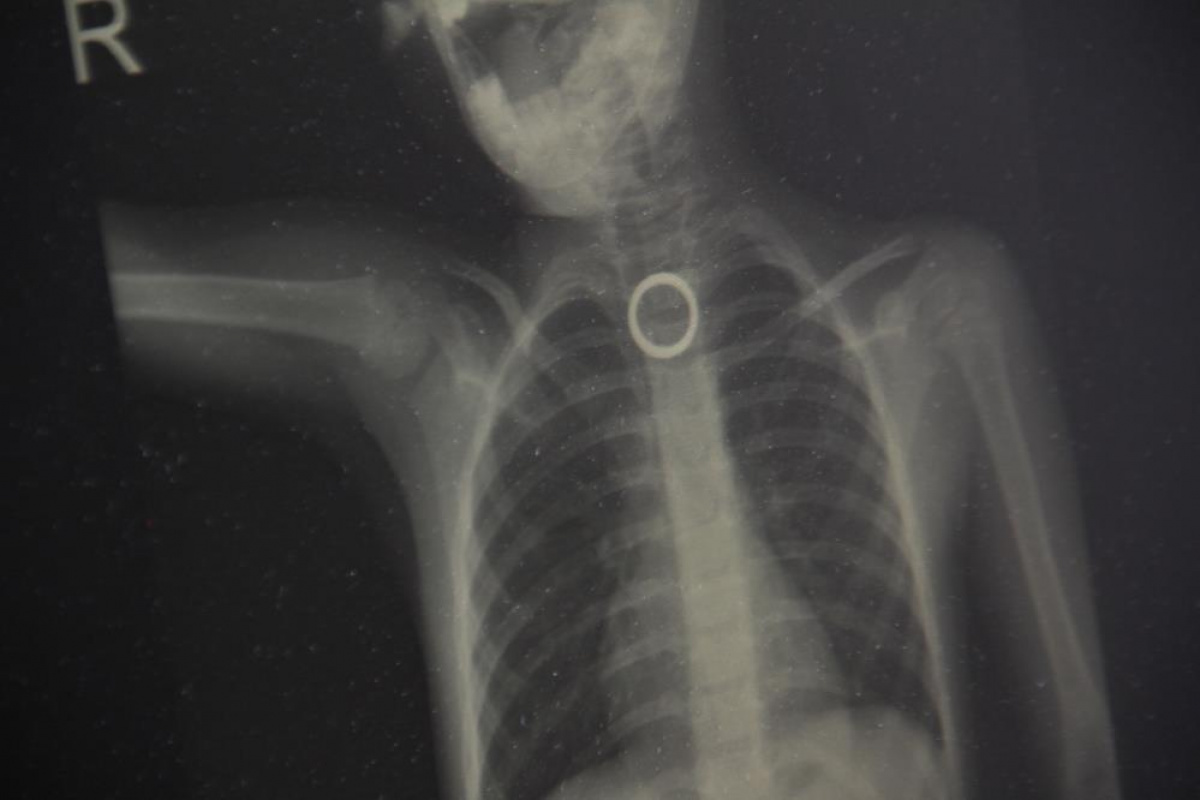

Oyun oynarken yerdeki yüzüğü yutan 3 yaşındaki çocuk ölümden döndü

Elazığ’da 3 yaşındaki çocuğun yutması sonucu yemek borusuna sıkışan yüzük, yapılan cerrahi operasyonla çıkartıldı.